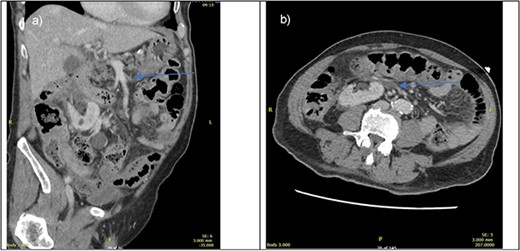

On presentation, his physical examination revealed an acute abdomen with generalised peritonism. Computed tomography (CT) angiogram of the abdomen suggested a thrombus in a distal branch of the superior mesenteric artery (SMA) without evidence of bowel compromise (Fig. 1). The preoperative provisional diagnosis for this patient was mesenteric arterial occlusion by arterial thrombosis. Differential diagnoses included mesenteric venous thrombosis, arterial embolism, and non-occlusive mesenteric ischaemia.

CT portal venous phase (left—sagittal slice, right axial slice) of imaging done upon presentation. Blue arrow pointing towards suspected thrombus causing bowel ischaemia.